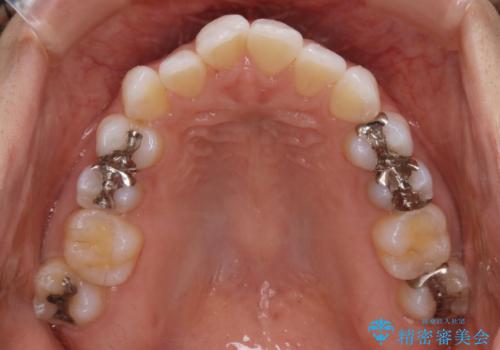

歯列弓の拡大

歯並びが悪くなる原因の一つに「歯列弓の狭窄」というものがあります。

奥歯や前歯が内側(舌側)に倒れ込んでしまったり、歯が生えてくる位置が内側になってしまうことにより歯並びのアーチが狭くなってしまうことを言います。

このような場合、歯並びのアーチを拡大してあげるだけでもガタつきを無くすためのスペースがかなり作れることがあります。

ディスキング(IPR)

歯のガタつきをとるためのスペース作りの方法の一つにディスキング(IPR)という方法があります。

歯と歯の間を一ケ所あたり最大0.5mmまでの範囲内で削ることで歯自体が少し小さくなり、それにより作られるスペースを数ヶ所分合わせることで合計で数mmの大きなスペースが作れるという方法です。

当院ではなるべく歯の機能や見た目に影響の出ないよう、作業時に拡大鏡の使用や削るタイミングの微調整を行っています。